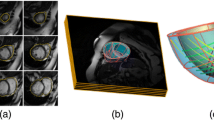

The anatomy and motion of the heart and the aorta are essential for patient-specific simulations of cardiac electrophysiology, wall mechanics and hemodynamics. Within the European integrated project euHeart, algorithms have been developed that allow to efficiently generate patient-specific anatomical models from medical images from multiple imaging modalities. These models, for instance, account for myocardial deformation, cardiac wall motion, and patient-specific tissue information like myocardial scar location. Furthermore, integration of algorithms for anatomy extraction and physiological simulations has been brought forward. Physiological simulations are linked closer to anatomical models by encoding tissue properties, like the muscle fibers, into segmentation meshes. Biophysical constraints are also utilized in combination with image analysis to assess tissue properties. Both examples show directions of how physiological simulations could provide new challenges and stimuli for image analysis research in the future.

Nickisch H, Barschdorf H, Weber FM, Krueger MW, Dössel O, Weese J (2012) From image to personalized cardiac simulation: encoding anatomical structures into a model-based segmentation framework. Lecture Notes in Computer Science (STACOM) (accepted)

Smith N, de Vecchi A, McCormick M, Nordsletten D, Camara O, Frangi AF, Delingette H, Sermesant M, Relan J, Ayache N, Krueger MW, Schulze WHW, Hose R, Valverde I, Beerbaum P, Staicu C, Siebes M, Spaan J, Hunter P, Weese J, Lehmann H, Chapelle D, Razavi R (2011) euHeart: personalized and integrated cardiac care using patient-specific cardiovascular modelling. Interface Focus 1(3):349–364